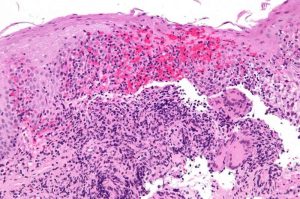

(Crhon-Immagine:DNA. Credito: Charles Clegg).